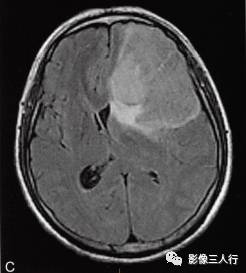

左侧额颞叶多形性胶质母细胞瘤

A.T1WI横断面;B.T2WI横断面;CFLAIR横断面;D.T1WI增强;E.T1WI增强冠状面;F.T1WI增强矢状面;G.HE×40;H.GFAR( )×40

影像学表现:

左侧额颞叶见较大不规则囊实性肿块,大小约5.4cm×8.3cm,平扫T1WI呈低信号、T2WI呈高信号(图A、B),肿块内有斑片状囊变区;增强扫描肿块实性部分呈不均匀明显强化,囊性部分呈环形强化(图D~F)。肿块占位效应明显,周围见环形水肿(图C)。